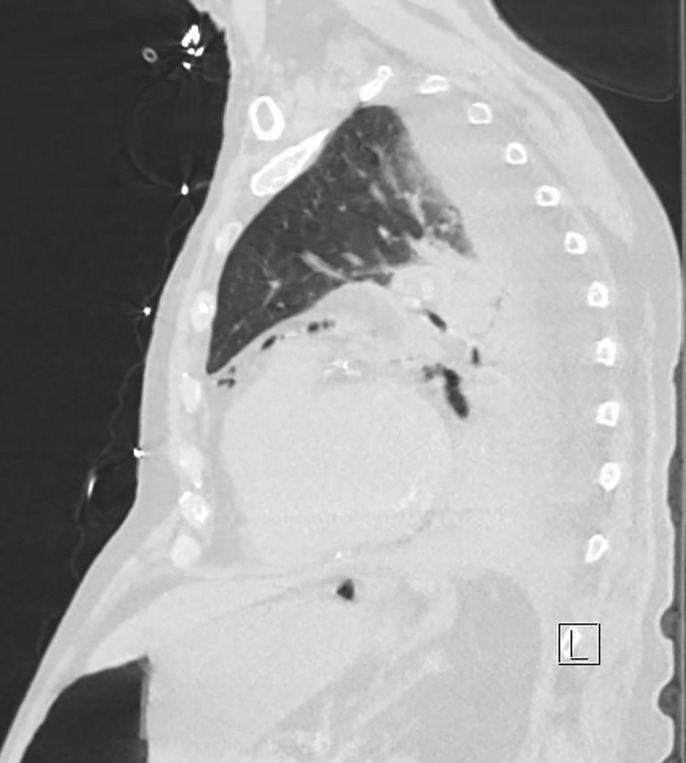

On admission day two, he developed acute abdominal distension and coffee ground emesis. Gastroenterology was consulted and further investigations into the patient’s history revealed vomiting with each episode of syncope. WBC at that time was elevated to 14.57 × 103 μ/L from his baseline of 7.21 × 103 μ/L on admission. Computed tomography with oral contrast revealed pneumomediastinum with a 3.6 × 6.9 cm air-fluid collection immediately adjacent to gastroesophageal junction on the left and several other foci of predominantly gas posterior to the gastric cardia which partially filled with small amount of contrast on postcontrast images (Figures 2–5). The diagnosis of esophageal perforation was made at that time. The patient was intubated, a nasogastric tube was inserted, and a temporary transvenous pacemaker was placed prior to transfer to our hospital for emergent repair of the esophagus.

Figure 3.

Sagittal view of pneumomediastinum and small focus of free air under the diaphragm from esophageal perforation.